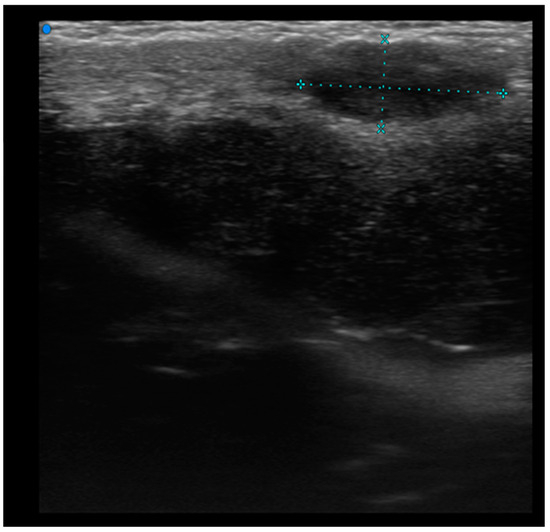

Figure 5. Focal pseudonodular lesion (T-cell lymphoma). Examination performed with a very high-frequency ultrasound probe at 48 MHz in the region of the right scapula: Iso-hypoechoic lesions with regular margins and epidermal localization.

Single or multiple hypoechoic nodules (Figure 2) with focal epidermal–subepidermal involvement, featuring regular margins without peripheral infiltration, were typical of B-cell lymphoma (Figure 3 and Figure 4).

Pseudonodular and nodular lesions were more frequently observed in B-cell lymphomas (70%), while diffusely infiltrative lesions were equally prevalent in both B-cell and T-cell lymphomas (50% each) (Figure 5).